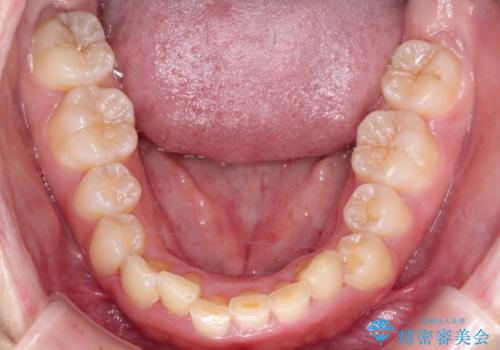

- 前歯の凸凹と深い噛み合わせを主訴に来院されました。

下の前歯が見えないほどのディープバイト症例でした。

ワイヤー矯正にて下顎前歯の圧下と臼歯部の挺出を効率的に行うことができました。